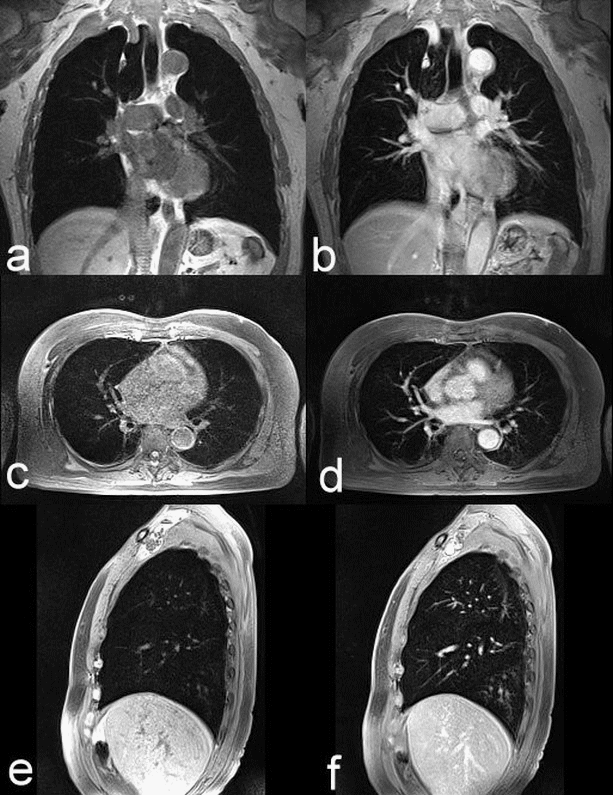

Chụp cộng hưởng từ lồng ngực có tiêm thuốc đối quang từ giúp tăng độ tương phản của mạch máu và bác sĩ có thể đánh giá được mức độ tưới máu của mô thông qua thời gian ngấm thuốc đối quang từ (từ động mạch qua mao mạch tại mô khảo sát và về lại tĩnh mạch). Vì vậy, các bệnh lý liên quan đến lồng ngực cần đánh giá vị trí, kích thước, mật độ và mức độ cấp máu chụp cộng hưởng từ có tiêm thuốc đối quang từ rất có giá trị trong chẩn đoán và tiên lượng điều trị.

- Phim chụp cộng hưởng từ phải đạt được những tiêu chuẩn hiện hình rõ các cấu trúc giải phẫu vùng ngực trên các chuỗi xung được lựa chọn;

- Phát hiện vị trí, kích thước, mật độ của tổn thương và đánh giá mức độ ngấm thuốc đối quang từ ở mô cần khảo sát;